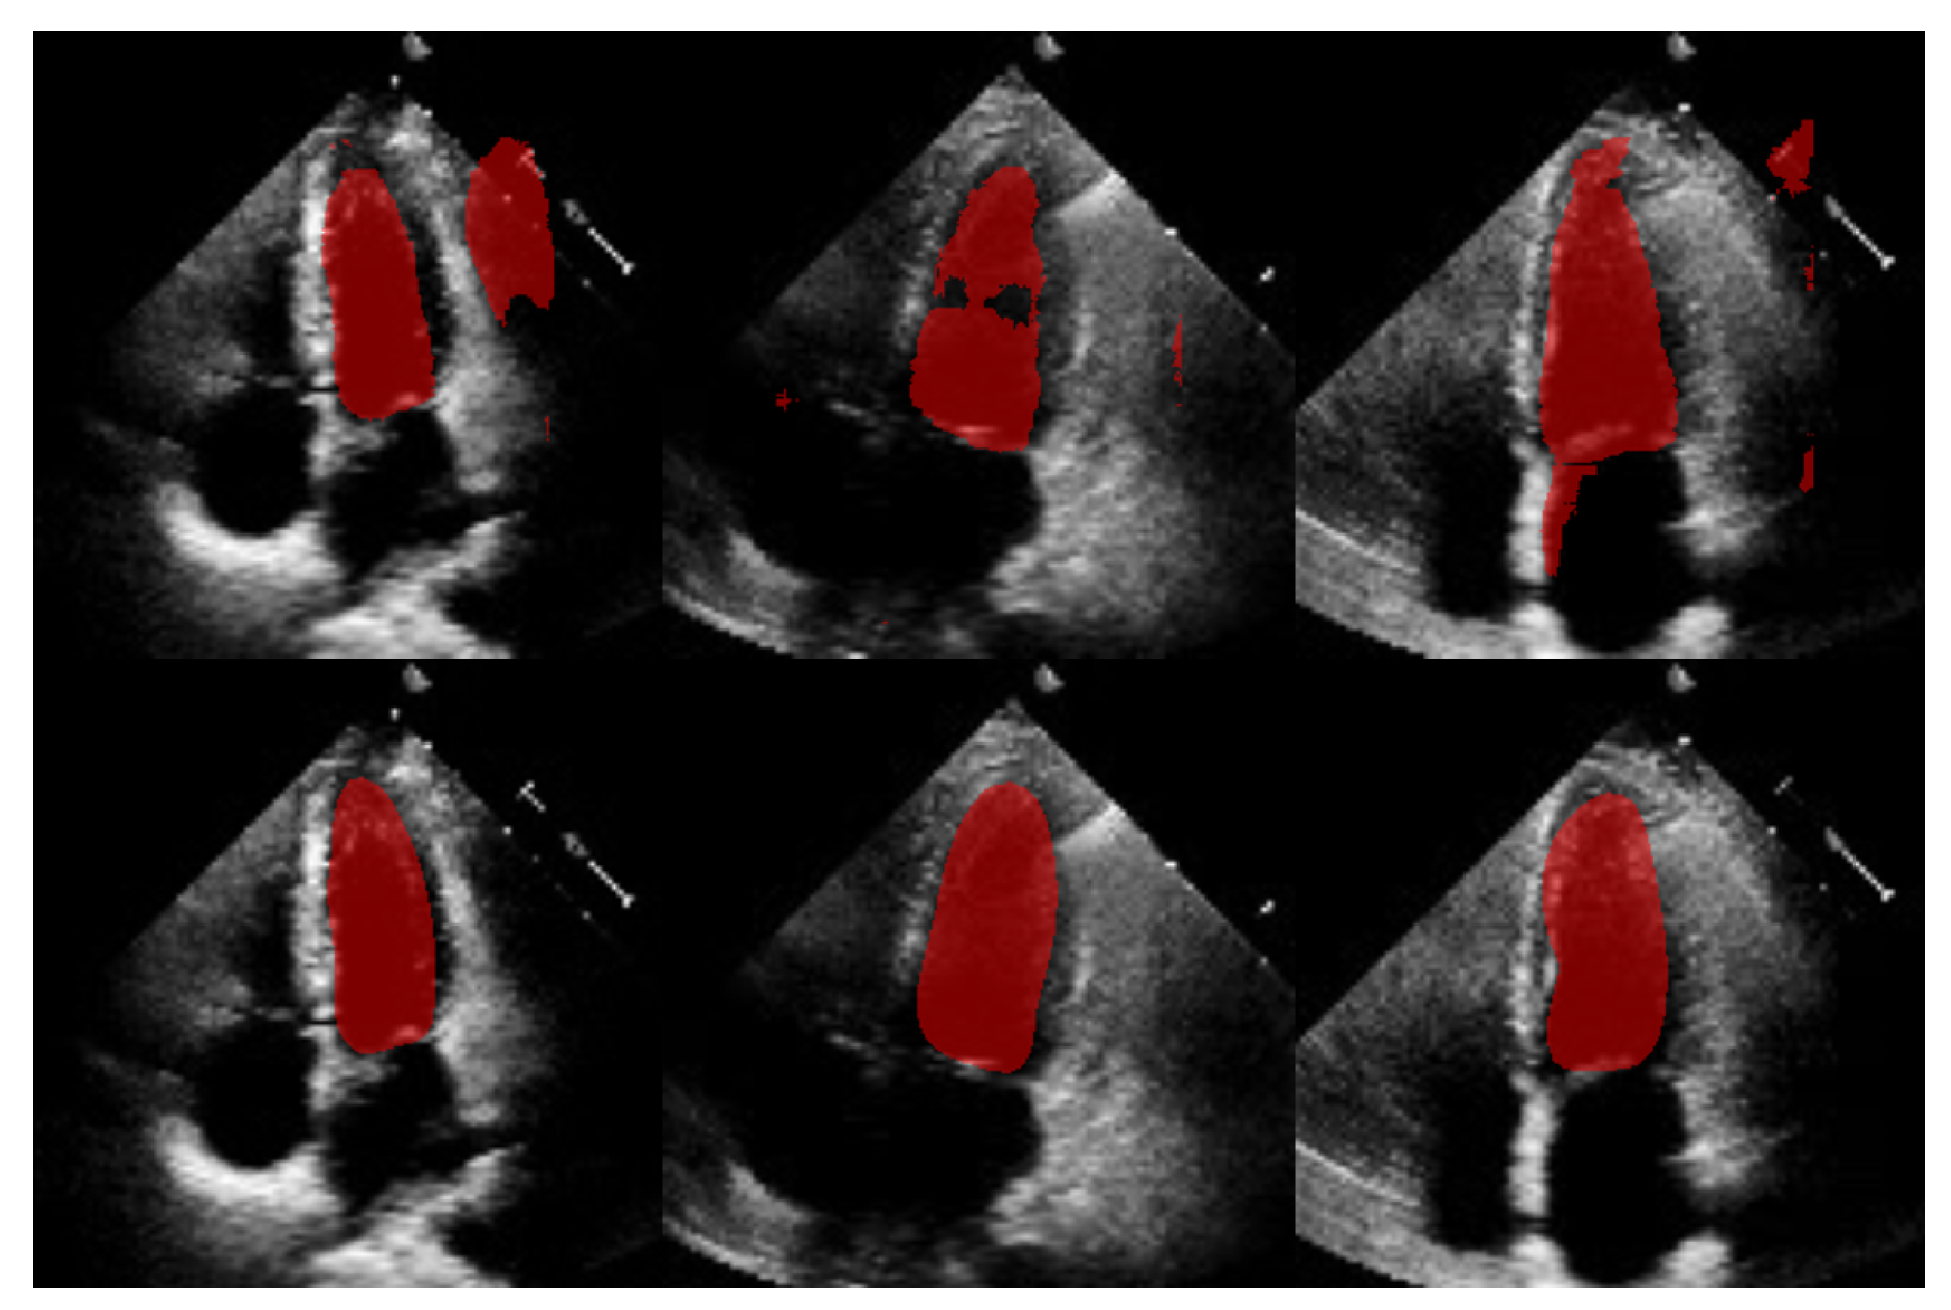

4.3. ShapeNet Contour Prediction Results

In this section, we present the results obtained from the reconstruction of the LV using the parameters predicted by ShapeNet, following the algorithm shown in Figure 8. To evaluate these results, we used the Dice coefficient and Hausdorff distance (HD) expressed in pixels (px), compared against expert annotations. Table 2 shows the Dice and Hausdorff values for the two test datasets: EchoNet and CAMUS. In Figure 11 and Figure 12 are shown six examples of LV reconstruction for systole and diastole, respectively.

Figure 11.

ShapeNet standalone systole segmentation examples for CAMUS (top) and EchoNet (bottom) images.

Figure 12.

ShapeNet standalone diastole segmentation examples for CAMUS (top) and EchoNet (bottom) images.

The approach implemented in ShapeNet, where the parameters of a statistical shape model of the organ of interest are optimized with a convolutional neural network, provides restrictions that contribute to the explicability of the final segmentation results. All shapes produced were statistically valid organ shapes. As observed in Figure 11 and Figure 12, the results were always smoothed ventricle shapes located closely to the LV in the echocardiography, with a scale and rotation approximate to the expert annotation. However, for deformations, in some cases, the predicted values of the deformation vector b were not as accurate, which was reflected in a higher Hausdorff distance (see Table 2).